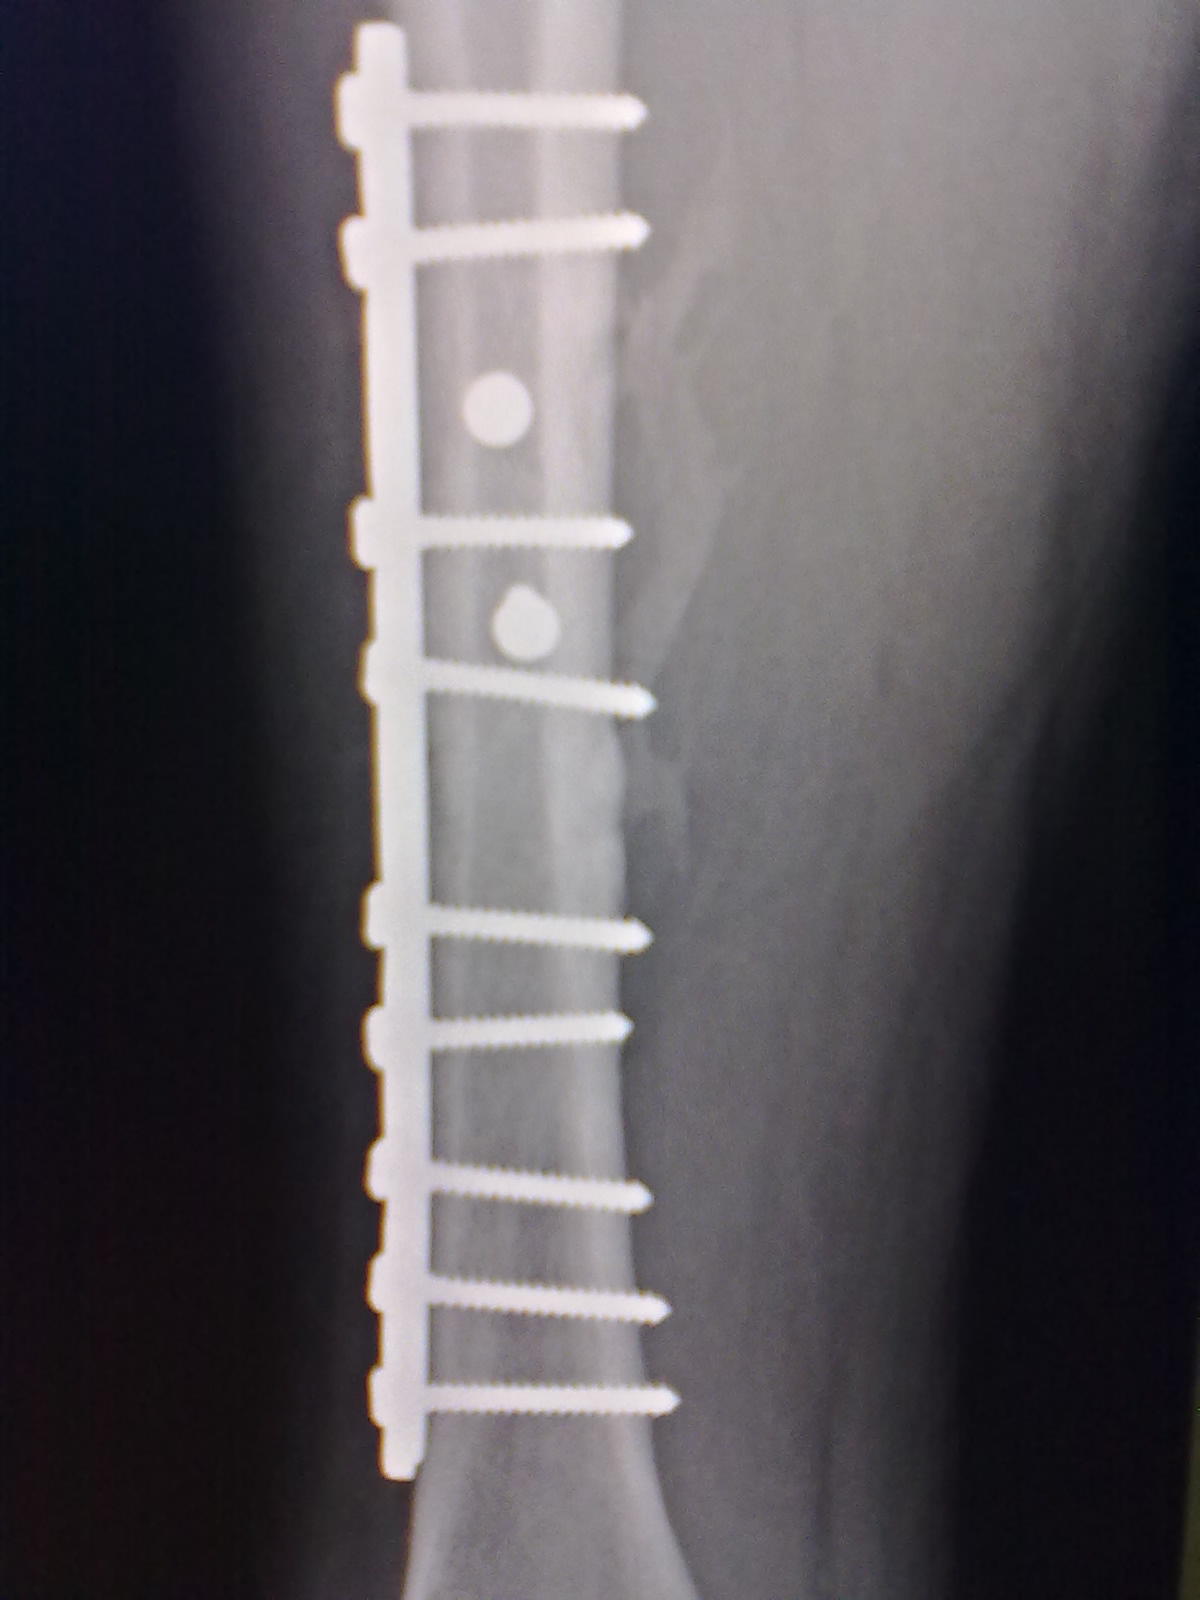

标题: X7065:M,30Y。股骨骨折内固定术后5个月复查片。 [打印本页]

标题: X7065:M,30Y。股骨骨折内固定术后5个月复查片。

外生骨痂还是骨化性机炎?

外骨痂形成。

不好鉴别,需要老片(3-6周时)对比。

二者都有

外骨痂与骨化性肌炎,都能解释。随骨折愈合可消失。

外骨痂及骨化性肌炎。

可能两者介有之。

骨化性肌炎

骨化性肌炎可能。

考虑外骨痂,与临床较相符。

外骨痂及骨化性肌炎两者有之。